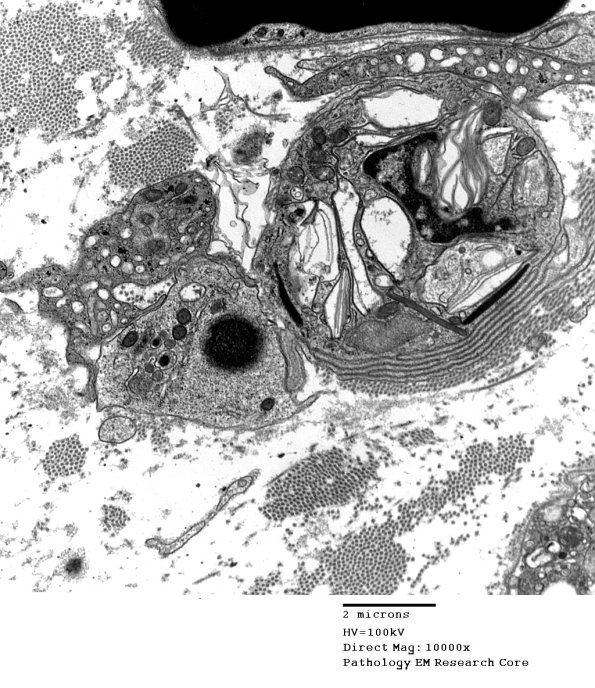

3D1,2 Two images of macrophage processes surrounding a later stage of a Schwann cell with a modest amount of residual debris.